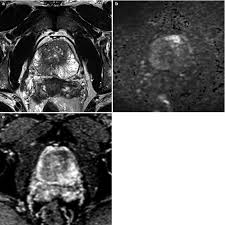

Revisiting Quantitative Multi Parametric Mri Of Benign Prostatic Hyperplasia And Its Differentiation From Transition Zone Cancer Springerlink

Revisiting Quantitative Multi Parametric Mri Of Benign Prostatic Hyperplasia And Its Differentiation From Transition Zone Cancer Springerlink from media.springernature.com